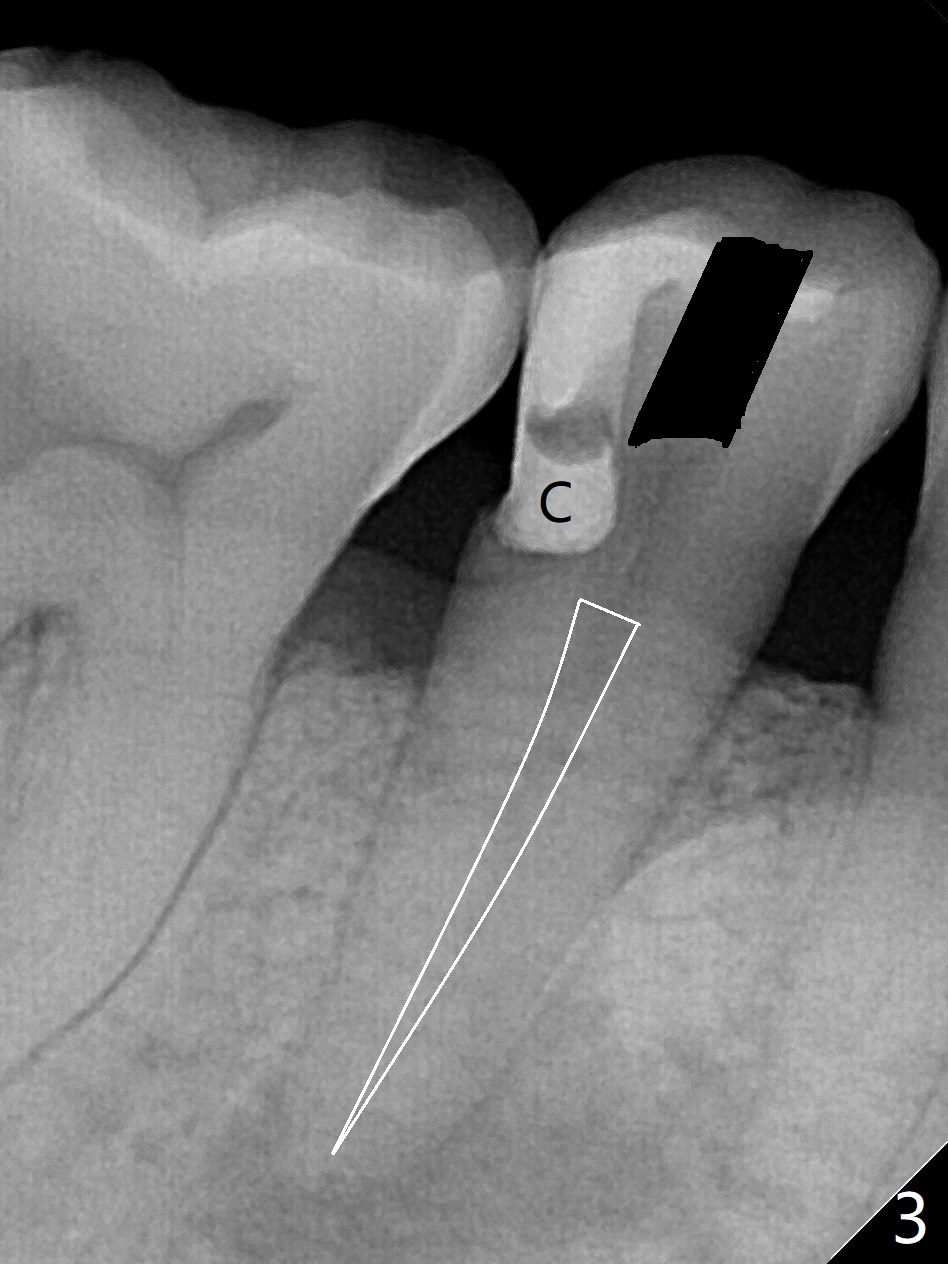

A 48-year-old man, dental phobic, wants minimal dentistry. The tooth #29 has large periapical radiolucency, extending mesial (Fig.1 *) and a fistula, apparently associated with the tooth #28 (Fig.2 *). The single canal has been debrided with 30/.06 rotary file and medicated with CaOH paste. To avoid microleakage without crown, gutta percha (Fig.3 white outline) will be cut apical to the distooclusal compostie (C). The fistula shrinks with no discharge 16 days post application of Calcium Hydroxide paste (Fig.4). RCT will be finished 2-3 weeks.